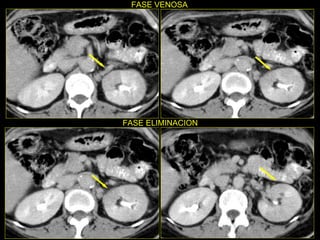

Caso # 3 ♀ , 5ta década de la vida.  Su síntoma principal fue dolor abdominal y por ello se le realizó un estudio de Urografía Excretora.  En él se sospecha de malformación arteriovenosa por lo que se envía a AngioTC. Se muestra estudio en fase simple, arterial, venosa y excretora, con cortes axiales y RMP coronales .

Hallazgos Caso # 3: Estudio negativo para la sospecha clínica que motivó su realización. Y en el que se demuestra, en la fase simple sin anormalidades, y posterior  a la ministración del medio de contraste hay un área hipodensa triangular en polo superior del riñón izquierdo, la cual se mantiene durante las fases arterial y venosa del estudio.